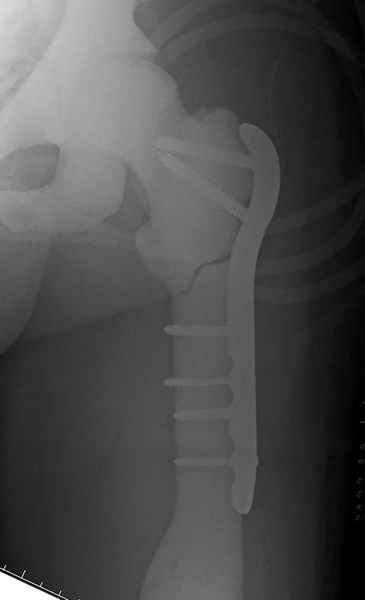

После неудачной попытки скелетного вытяжения в первом мед.учреждении, после осмотра снимков и изучения истории, поставили диагноз “Остеопетроз” или мраморная болезнь, редкая наследственная костная паталогия, где имеется нарушение формации остеокластов.

Конечно, было бы идеальным применение интрамедуллярного остеосинтеза, но учитывая прежний собственный опыт (лечил перелом бедра) и

публикации, предупреждающие о трудностях при обработке кости (иногда из-за неподготовленности инструментария результатом была неадекватная фиксация перелома, или перенос операции из-за фактора усталости оперирующего персонала), решили применить пластину (и в этом же случае был выбран Synthes plate, так что представитель за два дня

зароботал... на десерт тоже).

Заказаны были дополнительные различные дрели, и на следующий день, усиленной бригадой, больного прооперировали, потратив на каждое отверстие около 25-35 минут, хотя сверлили с охлаждением по нарастающей по диаметру сверл и с их заменой каждые 2 мм сверления.

Теперь стоит задача со сращением перелома, из-за отсутствия литературных данных по применению костных стимуляторов при остеопетрозе, и не зная как поведет в этой среде Grafton, все таки надеюсь, что даст толчок к стимуляцию, решил применить пастообразную деминерализованную костную матрицу, расположив спереди между отломками.